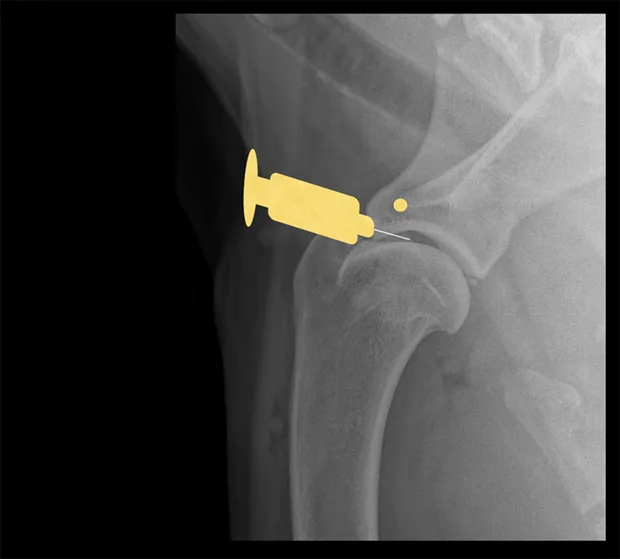

Hip

Place the patient in lateral recumbency with the hip upward in slight abduction and slight external rotation. Insert a 22- or 20-gauge, 3-inch spinal needle just dorsal to the greater trochanter, and enter the joint in a lateral-to-medial direction. For a ventral approach, insert the needle just caudal to the pectineus muscle over the hip joint, directed at a 45° angle in a craniodorsal direction. Some resistance may be felt as the needle is passed through the ventral joint. Ultrasound guidance is helpful but not essential.

Lateral view of pelvis. Insert the needle at the proximal extent of the greater trochanter into the hip joint in a lateral-to-medial direction.